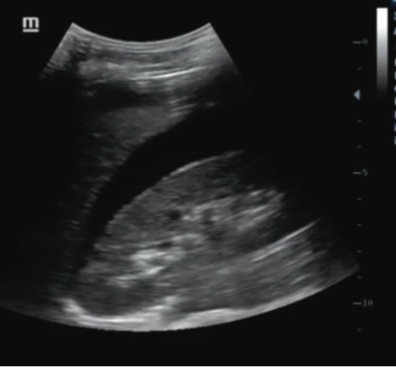

Q

Liquido livre

Aspecto no USG?

A

Imagem anecoica que contorna orgãos, dando aspecto de semilua